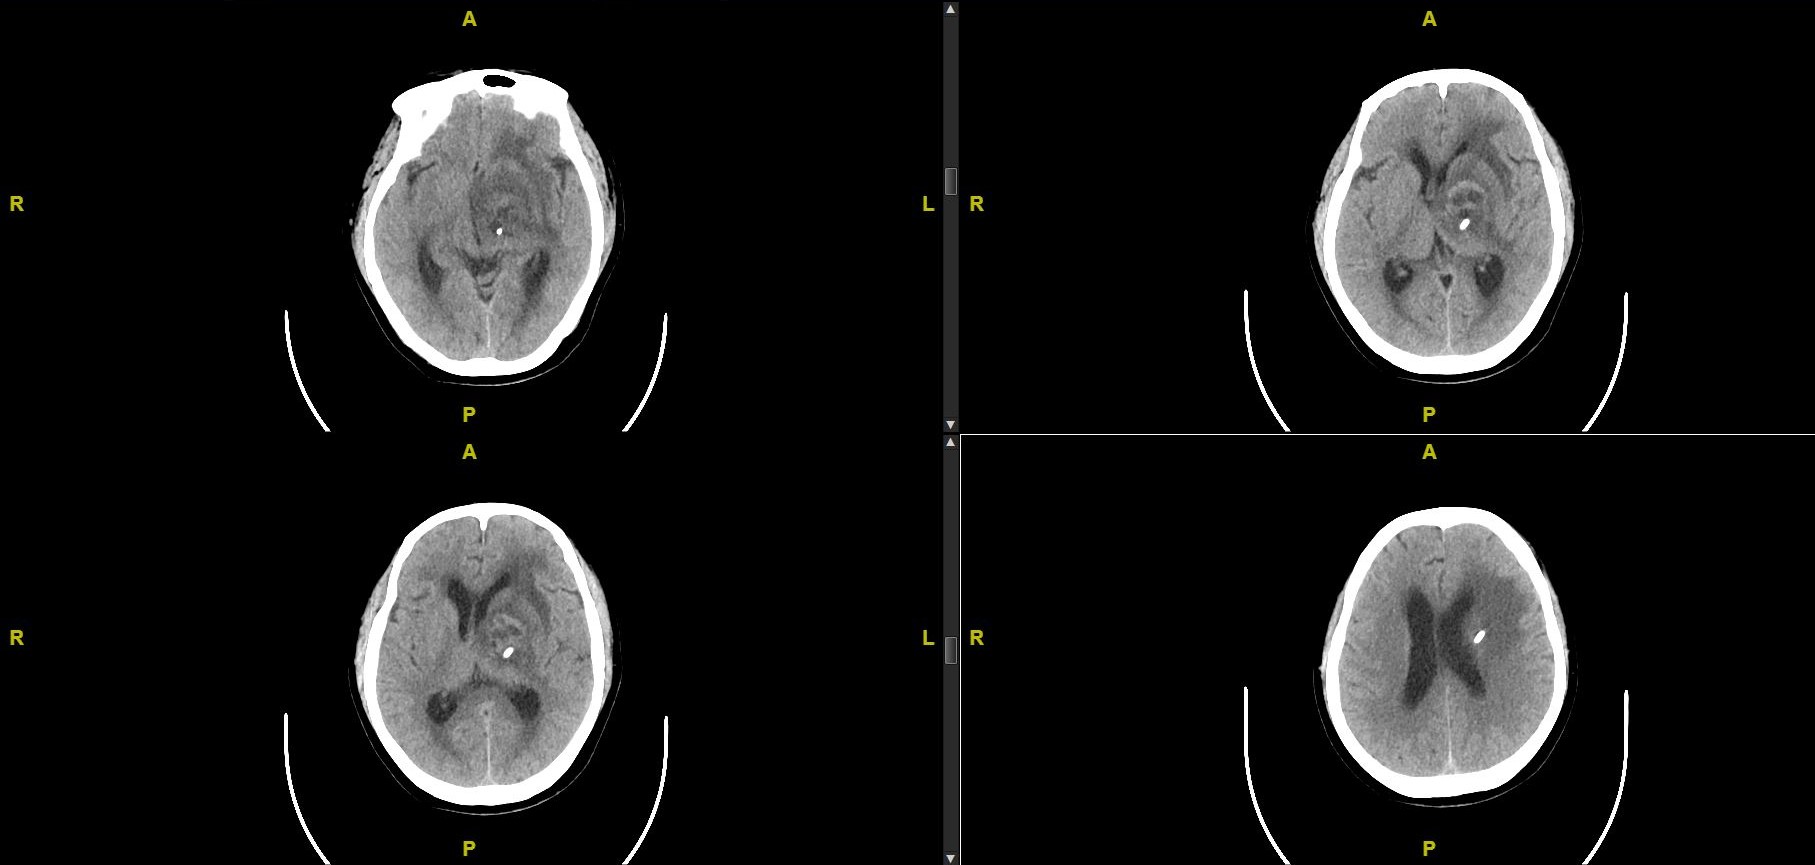

给予患者左侧基底节区囊肿欧马亚囊植入术,术后抽吸囊液3次,左侧囊性肿瘤基本完全消失。患者头痛症状明显缓解,语言较前流利,术后CT如下:

术后CT囊腔消失